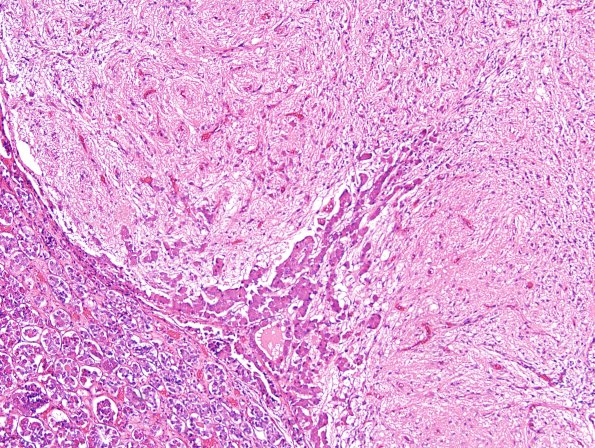

6F Pituitary, normal H&E basopil invasion

An additional example of basophil invasion in the current cases. (H&E)